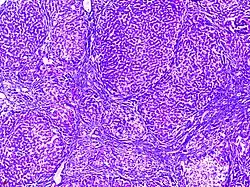

![]() | Seminoma testis | Micrograph of seminoma testes showing lobules of uniform cells separated by delicate septae of fibrous tissue. These cells can have a distinct outline with clear cytoplasm. The nuclei are large, with central prominent nucleolus. | Category: Histopathology of testicular seminoma | seminoma |